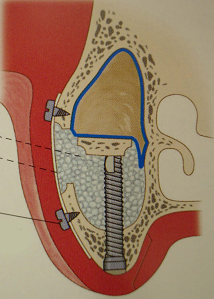

明日は久しぶりにサイナスリフトのオペが入っている。しょっちゅうあるわけではないので、オペ前には感覚を戻すために、必ず生卵で練習している。生卵で100発100中うまくいけば、臨床では100パーセントうまくいくという話もあるが、臨床の方がいろんな制約があって(出血するとか、見ずらいとか)、結構大変だ。高速回転の昔ながらの機械で、生卵の中の膜を破らずに窓開けをする。生卵の殻が実際の臨床では顎の骨に相当する。最近はピエゾサージェリーなる超音波の機械がはやってきて窓開けも楽ちんになったという話をよく聞く。今日バイトに来てたN先生に聞いたら、「医科歯科大インプラント治療部ではピエゾから昔のやり方に戻った」とのこと。やはり手の感覚に勝るものは無いのか?2002年にミシガン大学に行ってまで覚えたこの手術。患者さんごとに解剖学的構造が異なるので、ちょっと慣れたからと言って舐めてはかかれない。前の晩は妙に緊張する。さあ早く寝よう。

生卵でサイナスリフトの練習